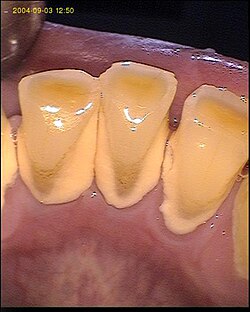

Zubni kamenac nastaje nakupljanjem anorganskih tvari (minerala) u plaku. Mineralizacija plaka nastaje uglavnom u predjelima gdje se nalaze izlazi velikih žlijezda slinovnica: parotidna žlijezda bukalno u predjelu molara, sublingualna žlijezda – lingualno u predjelu inciziva. Mineralizacija nastaje jer je slina preplavljena sa kalcijom. Zubni kamenac je građen u obliku lamela, što dokazuje da nastaje kroz duže razdoblje.

Sam kamenac nije kariogen niti je uzrok parodontitisu, ali bakterije i plak koji se na kamencu nakupljaju i u njemu nalaze, su faktori nastanka navedenih bolesti.[1]